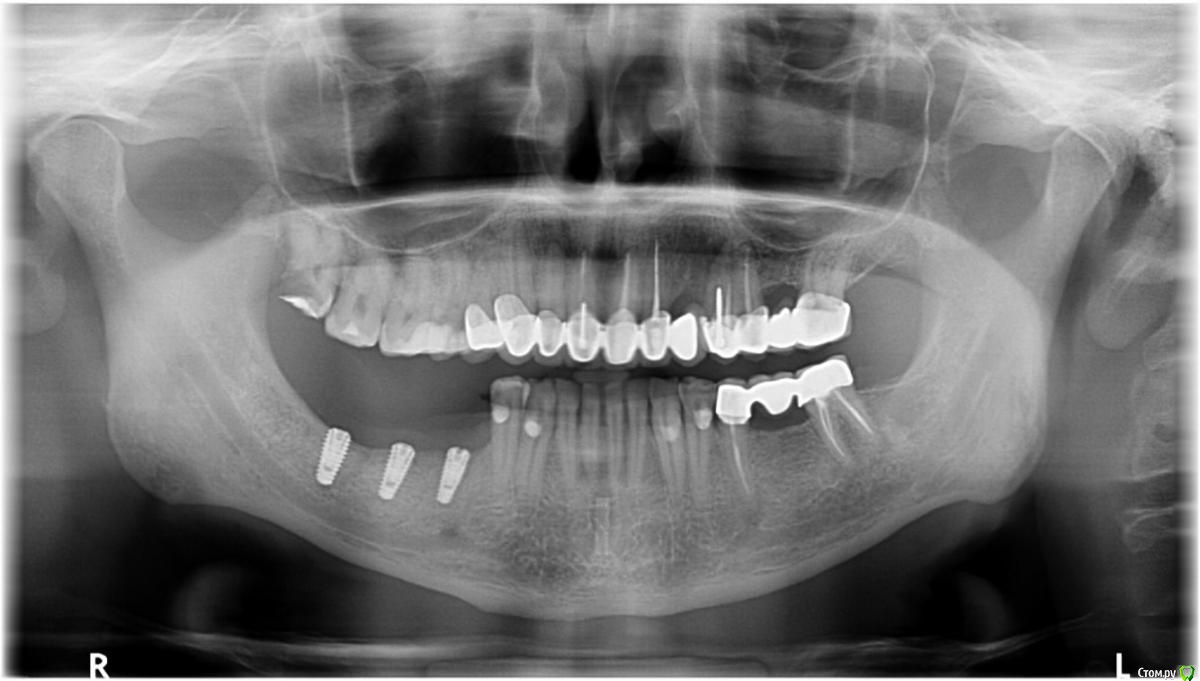

Orange1 Опубликовано 14 февраля, 2017 Поделиться Опубликовано 14 февраля, 2017 Здравствуйте коллеги.Проведена имплантация Megagen лето 2016.Ваше мнение по поводу обнажения витков.Помогите советом. Как С ними справиться.Спасибо! Ссылка на комментарий

Orange1 Опубликовано 14 февраля, 2017 Автор Поделиться Опубликовано 14 февраля, 2017 Вот такая проблема Ссылка на комментарий

stommm Опубликовано 14 февраля, 2017 Поделиться Опубликовано 14 февраля, 2017 1. Удалить 182. Шашлычки на формики, понаблюдать3 при необходимости повторить (как раз бугор заживет) 2 Ссылка на комментарий

DrNice Опубликовано 14 февраля, 2017 Поделиться Опубликовано 14 февраля, 2017 Согласен, если справится с ними, то шашлычек может помочь. Когда ставили, заглубили на какой уровень? Ссылка на комментарий

DrNice Опубликовано 15 февраля, 2017 Поделиться Опубликовано 15 февраля, 2017 Без обид. Сомнительно, что погружали. По логике погружение - это со стороны самой глубокой "стороны". Но тут проблем действительно не наблюдается особых. За шашлык + 1000. Что за система,если не секрет? Сомневаюсь в догадках. Здравствуйте коллеги.Проведена имплантация Megagen лето 2016.Ваше мнение по поводу обнажения витков.Помогите советом. Как С ними справиться.Спасибо! Да я тоже сомневаюсь в полном погружении, хотя они по протоколу должны погружаться. Ссылка на комментарий

Fibez Опубликовано 17 февраля, 2017 Поделиться Опубликовано 17 февраля, 2017 И зря 18-й не дернули. Было бы откуда десну брать Ссылка на комментарий

Orange1 Опубликовано 17 февраля, 2017 Автор Поделиться Опубликовано 17 февраля, 2017 Да я тоже сомневаюсь в полном погружении, хотя они по протоколу должны погружаться.Погружал.думаю сверхкомпрессия съела.сейчас бы делал с времянками.Вчера раскрылся.удалил 18.шашлычок на 4.5.наблюдаю жду результата.фото к сожалению не делал.спасибо за советы коллеги. Ссылка на комментарий